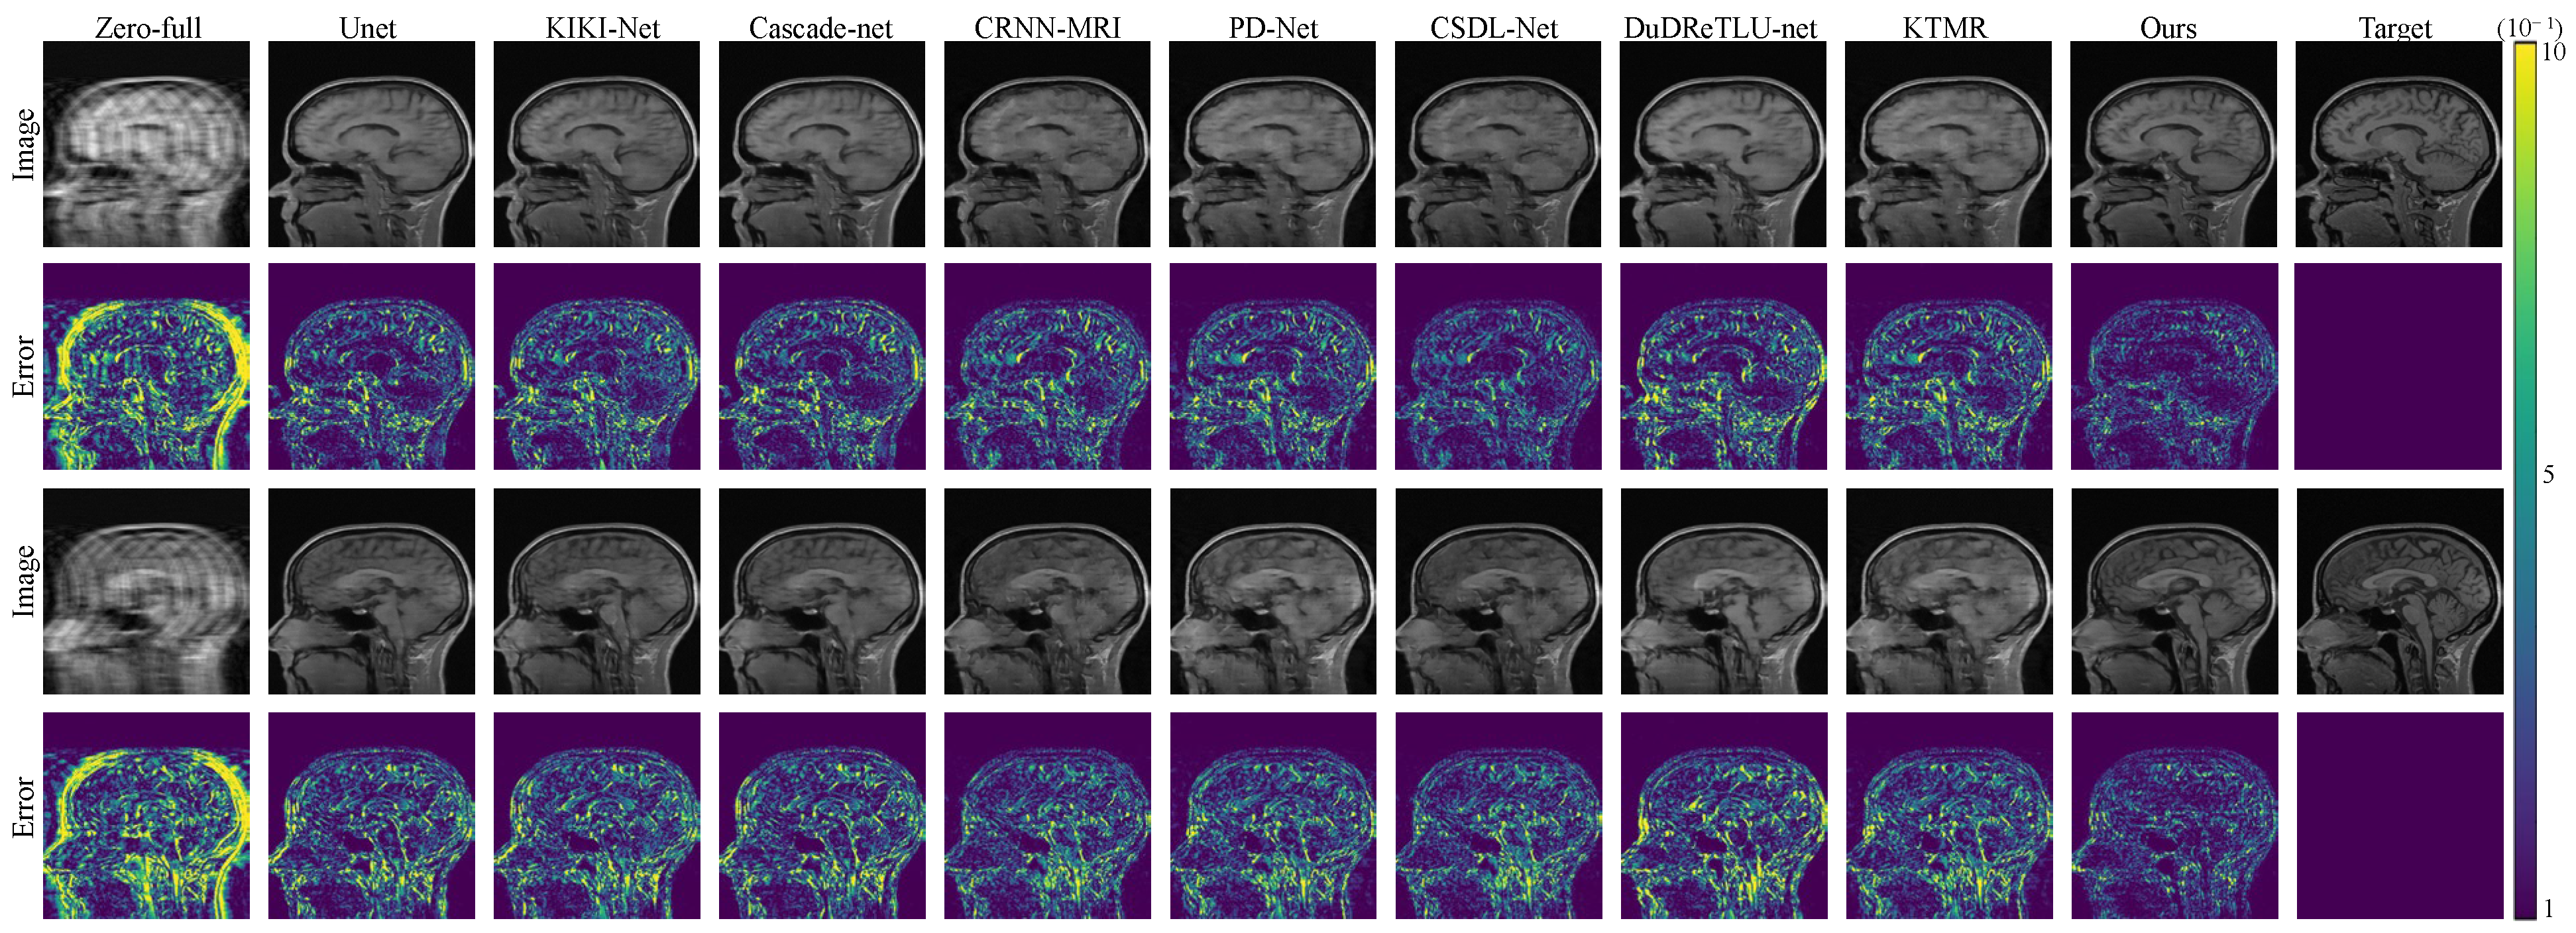

To visually illustrate the effectiveness of our approach, we present comparison results for 4× and 8× acceleration rates in Figure 2 and Figure 3. These figures clearly demonstrate that our framework excels in preserving intricate structures, creating more natural and intricate texture features, and producing clearer and more realistic reconstructed images compared to other methods. Furthermore, our method excels in achieving high-fidelity reconstructions even when dealing with highly under-sampled measurements. Figure 2 and Figure 3 also display error maps corresponding to various comparative methods, highlighting that our approach yields fewer errors at different under-sampling rates.

Figure 2. The reconstruction results and error maps are compared among 8 algorithms under 4× acceleration on the FastMRI dataset.

Electronics 12 04742 g002